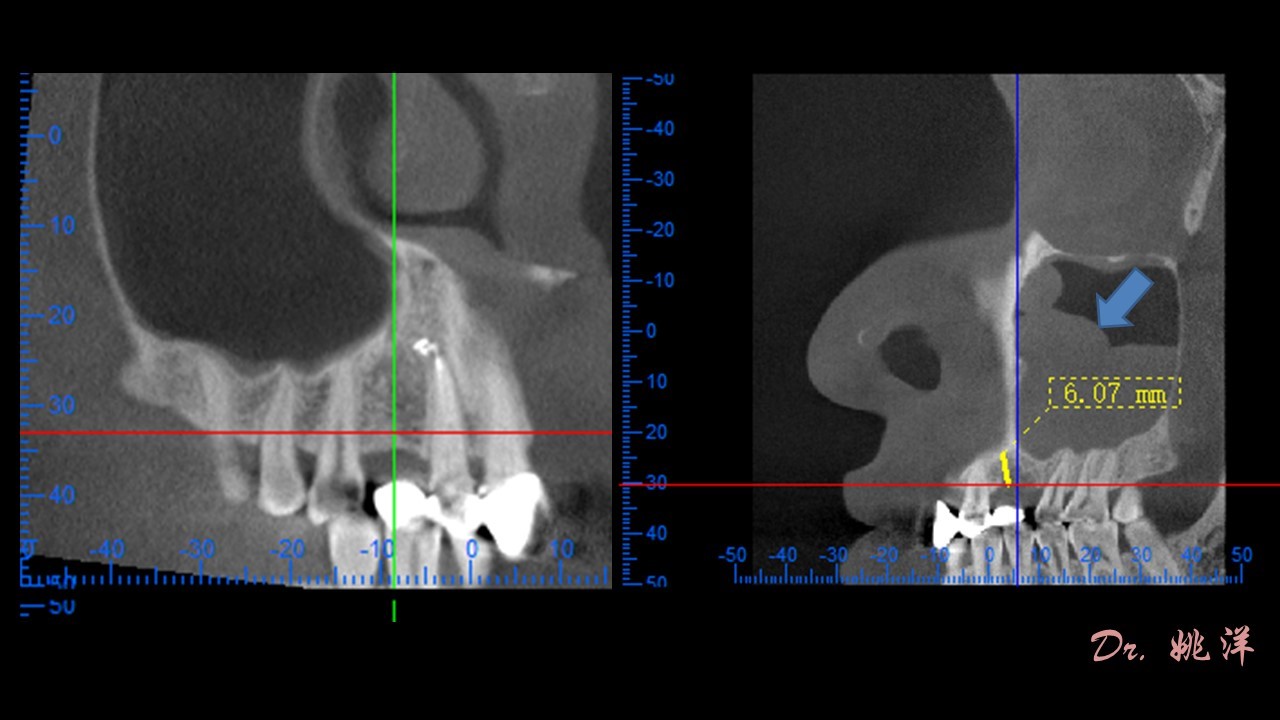

近年來,很多牙齒缺失的患者選擇了口腔種植,其實(shí)口腔種植不僅適用于牙齒缺失一次種植,還被廣泛用在烤瓷牙出現(xiàn)損壞而進(jìn)行二次種植修復(fù)中。 因?yàn)榭敬晒趽p壞,導(dǎo)致上頜竇囊腫或者牙槽骨吸收等狀況,而且二次修復(fù)對(duì)剩余牙...